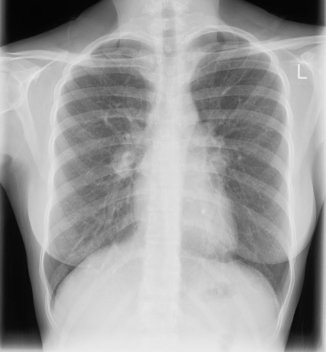

alterações radiográficas na TB pulmonar

A

• linfadenopatia hilar e/ou mediastinal

• derrame pleural

• consolidação pulmonar

How well did you know this?

principal achado radiográfico na TB pulmonar

Linfadenopatia hilar